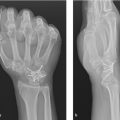

Total wrist arthrodesis is the gold standard treatment for the end-stage arthritic wrist. The procedure involves the fusion of radiocarpal, intracarpal, and sometimes the carpometacarpal joints. High rates of union (98%), satisfaction (96%), grip strength, and physical function underscore the value of the procedure. Total wrist arthrodesis is classically indicated in the higher demand patient with posttraumatic arthritis to include scapholunate advanced collapse and scaphoid nonunion advanced collapse. The procedure is also indicated for inflammatory arthropathy, salvage cases, segmental bone loss, and cerebral palsy. Fusion is most often commonly achieved with an anatomic spanning dorsal plate. The most common complication is tendon irritation. Despite this, the total wrist fusion provides a stable and functional wrist in the setting of advanced arthritis.

Total wrist arthrodesis involves the preparation and fusion of radiocarpal, intracarpal, and sometimes the carpometacarpal joints. Most surgeons prefer plate fixation but intramedullary devices are another option.

Posttraumatic arthritis of midcarpal and/or radiocarpal joints to include degenerative carpal collapse, following a scaphoid fracture non-union, scapholunate dissociation, or Kienbock disease.